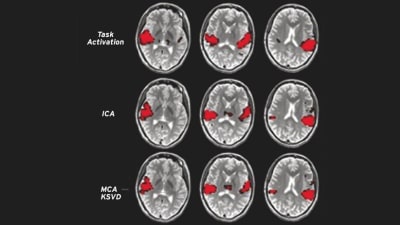

Spatiotemporal Imaging Exploiting Structured Sparsity

Spatiotemporal imaging contains a large class of imaging problems, which involve collecting a sequence of data sets to resolve both the spatial and temporal (or spectral) distributions of...